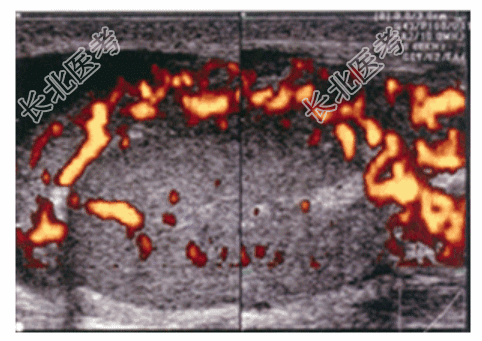

- 简答题2、血常规:白细胞20×10⁹/L;尿常规:白细胞500个/HP;阴囊彩色多普勒超声(图35):左侧附睾增大,血运丰富。目前考虑该患者的诊断可能为?